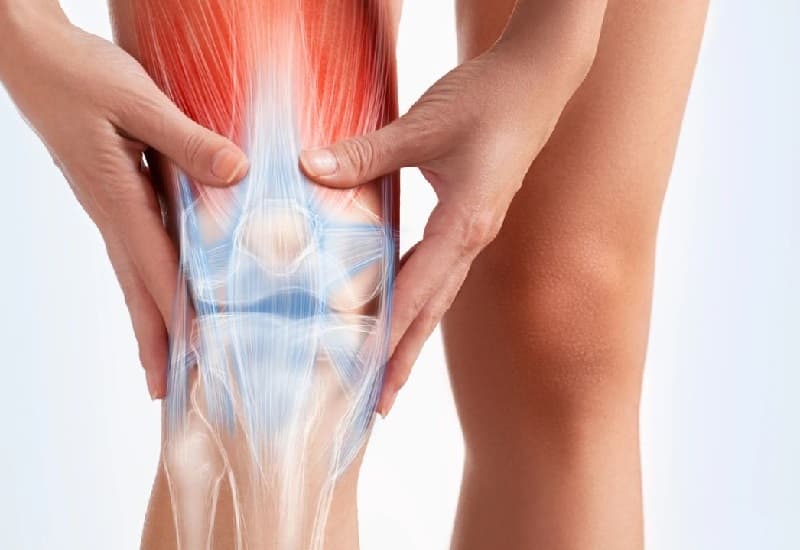

Khớp gối có chức năng chính trong việc nâng đỡ toàn bộ sức nặng của cơ thể và chịu áp lực lớn nhất khi nâng, vác các vật nặng. Chính vì vậy, khớp gối là bộ phận rất dễ bị tổn thương, viêm, sưng… Trong đó, thoái hóa khớp gối m17 là một bệnh lý thường gặp ở vùng khớp gối.

Quá trình thoái hóa khớp gối diễn ra khi lớp sụn khớp bị bào mòn, bong nứt khỏi phần xương dưới sụn. Khi người bệnh vận động khớp gối, hai đầu xương sẽ cọ xát trực tiếp vào nhau gây ra tình trạng đau nhức tại khớp gối.

Các cơn đau nhức này có thể trở thành mạn tính dưới tác động của bao hoạt dịch khớp cũng như sự hình thành gai xương ở rìa khớp gối. Cuối cùng quá trình này làm biến dạng khớp, gây ảnh hưởng trực tiếp đến chức năng vận động khớp gối.